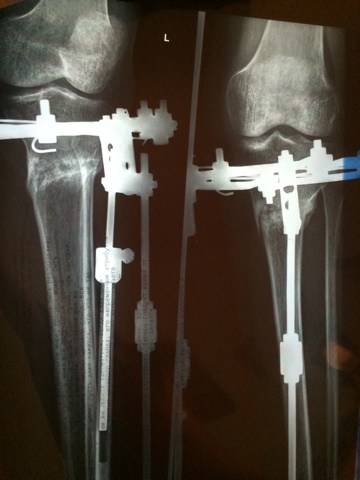

Рентген в 2 месяца.